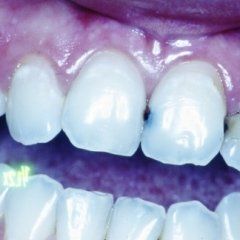

L’enorme diffusione ancora oggi riscontrabile della carie dentaria, unita a traumi, difetti di mineralizzazione o ipoplasie dello smalto determinano la necessità di dover ricorrere ad un restauro dei tessuti dentari lesionati. Il continuo miglioramento dei materiali e di conseguenza delle tecniche hanno altresì ampliato il raggio di azione della cosiddetta conservativa che con il ricorso al trattamento endodontico in caso di lesioni particolarmente gravi, occupa circa i due terzi dell’attività del dentista. In considerazione di questo fatto quindi, oltre all’evidenza che il trattamento restaurativo diretto è in genere il primo atto odontoiatrico che si effettua su una corona dentale lesionata, emerge la necessità che questa terapia sia ben eseguita ed in armonico rapporto con le strutture parodontali ed endodontiche.